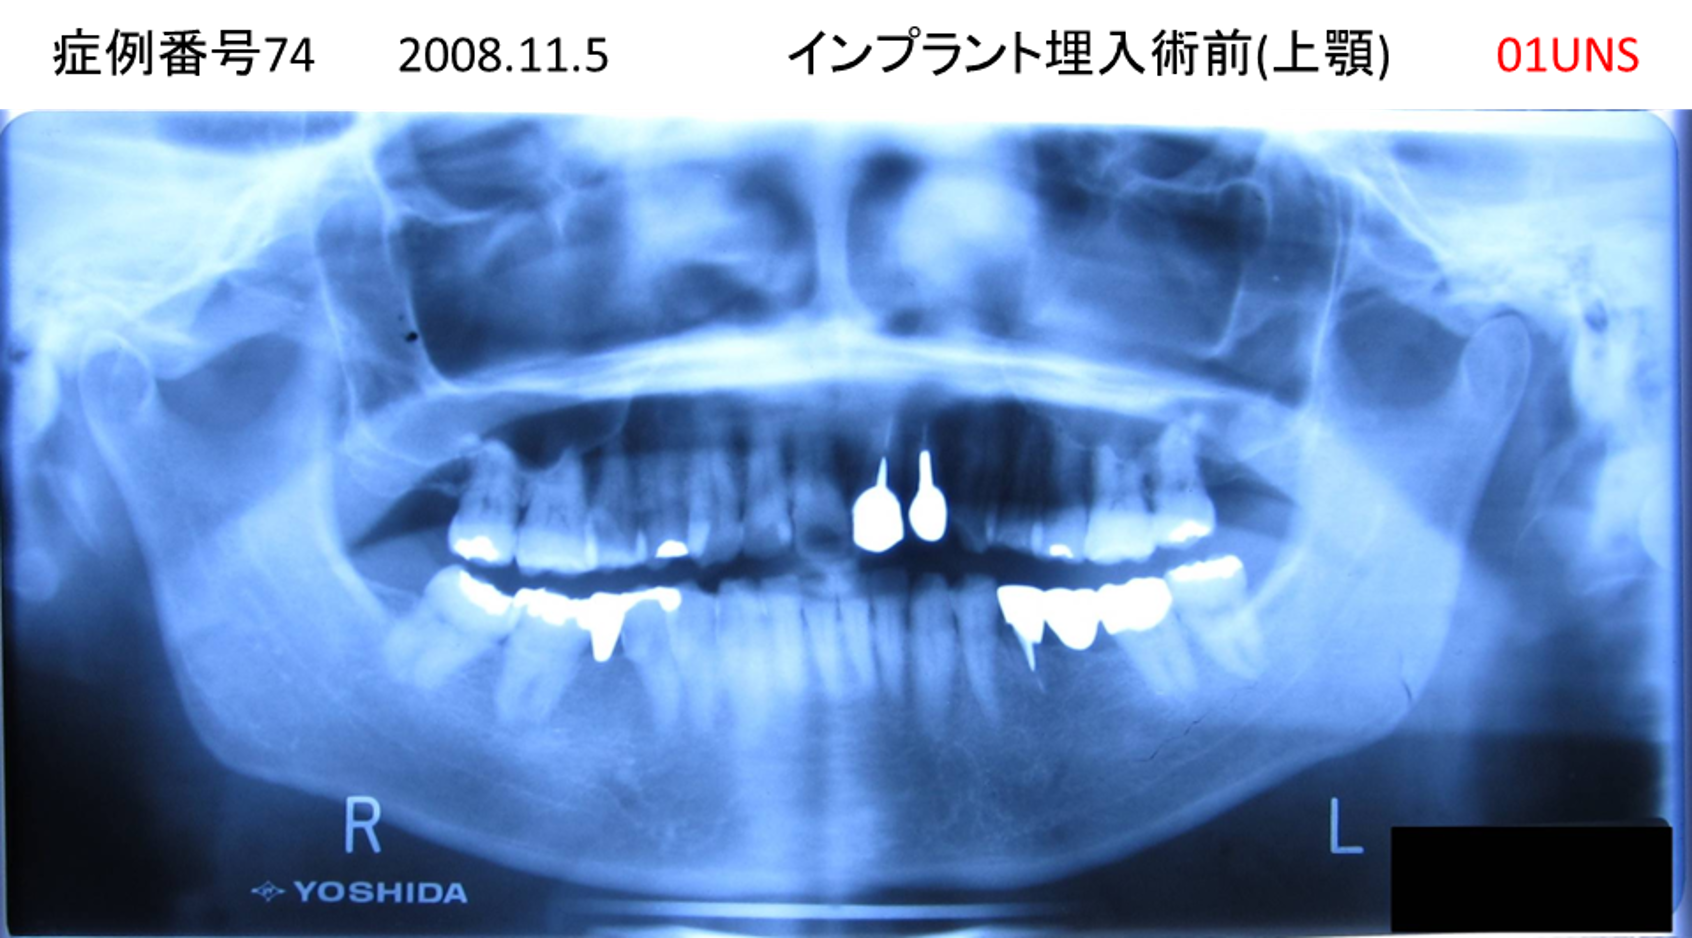

上の前歯が揺れていて痛い患者様のインプラント症例

| 治療名称 |

インプラント |

| 治療費用 |

295万円+税 |

| 治療期間 |

6か月 |

| 患者さんの症状(主訴) |

上の前歯が揺れていて痛い |

| 治療内容 |

抜歯即時インプラント |

| 治療結果 |

痛みがなく、しっかり噛める。 見栄えがとても良い |

| 治療の注意点(リスク/副作用) |

インプラントが壊れたら再治療が必要 |